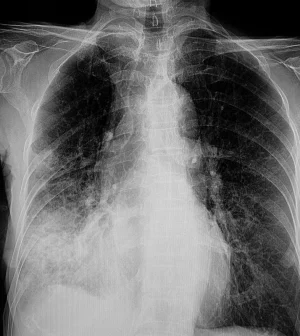

But there are two other types: Septicemic plague, which spreads throughout the body, and pneumonic plague, which infects the lungs.

Pneumonic plague, which caused the Arizona death, is also the easiest to spread, AP said.